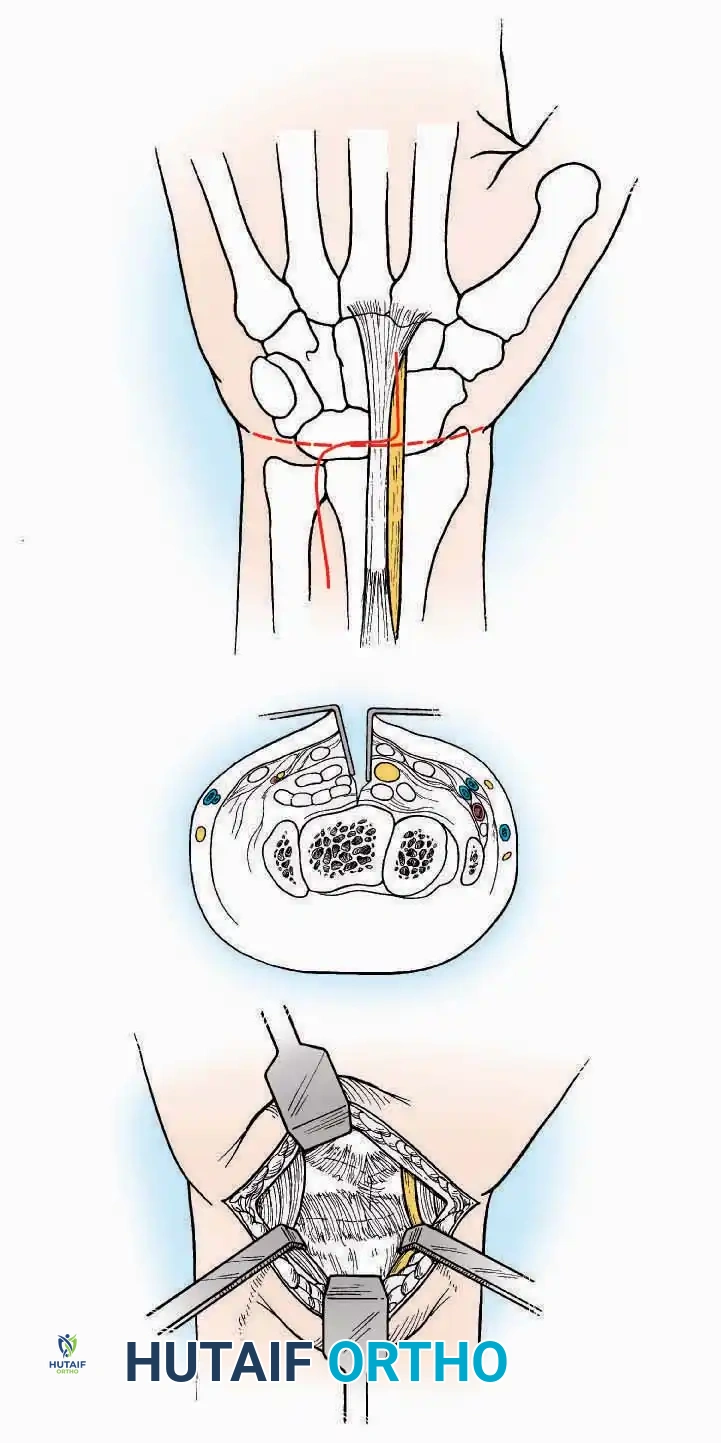

Anterior Approach

Indications: Total ankle arthroplasty (TAA), anterior ankle arthrodesis, and excision of anterior tibial/talar osteophytes (anterior impingement).

Surgical Technique:

* Incision: Make a 10 to 15 cm longitudinal incision over the anterior aspect of the ankle, centered exactly midway between the medial and lateral malleoli.

* Superficial Dissection: Incise the superficial fascia. Identify and protect the superficial peroneal nerve branches laterally and the saphenous nerve medially.

* Internervous Plane: The deep dissection exploits the plane between the Extensor Hallucis Longus (EHL) tendon (innervated by the deep peroneal nerve) and the Extensor Digitorum Longus (EDL) tendons (also innervated by the deep peroneal nerve).

* Neurovascular Bundle: Incise the extensor retinaculum. Carefully identify the anterior tibial artery and the deep peroneal nerve, which typically lie between the EHL and EDL, or directly deep to the EHL. Retract the neurovascular bundle laterally with the EDL, or medially with the EHL, depending on the specific anatomical variant encountered (lateral retraction is most common).

* Capsulotomy: Incise the anterior joint capsule longitudinally. Elevate the capsule subperiosteally from the anterior tibia and the talar neck to expose the entire tibiotalar articulation.